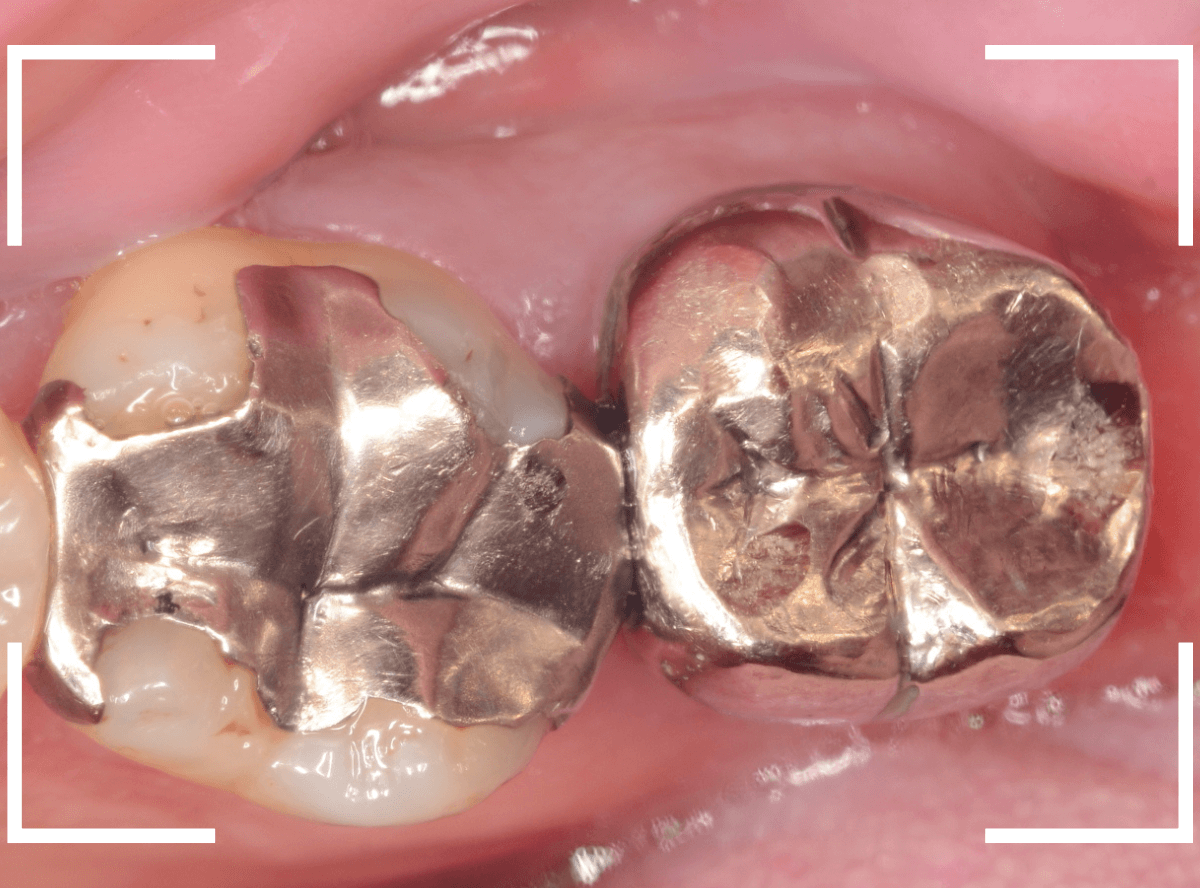

Case.11 メタル・インレー下の虫歯の治療後、ジルコニア・インレーへ

今回は、金属のつめもの(メタル・インレー)の下が虫歯になってしまった方をジルコニア・インレーで治療し直したケースです。

レントゲン写真で確認します。

金属の中と、隣の歯も虫歯になっているのがわかります。

金属を外して、中を確認します。

こういった場合は、下敷きになっているセメントの下も虫歯になっている事が多いので、セメントを全て外して虫歯になってないか、調べます。

う蝕検知液で確認しながら、虫歯を除去します。

このセメントは神経に近い所まで埋まっていますので、削りすぎないように慎重に除去します。

全ての虫歯を除去する事ができました。

治療前後の比較です。

比べてみると、白い歯の良さがわかると思います。

患者さんにも、喜んでいただき、いつもながらほっとしました。